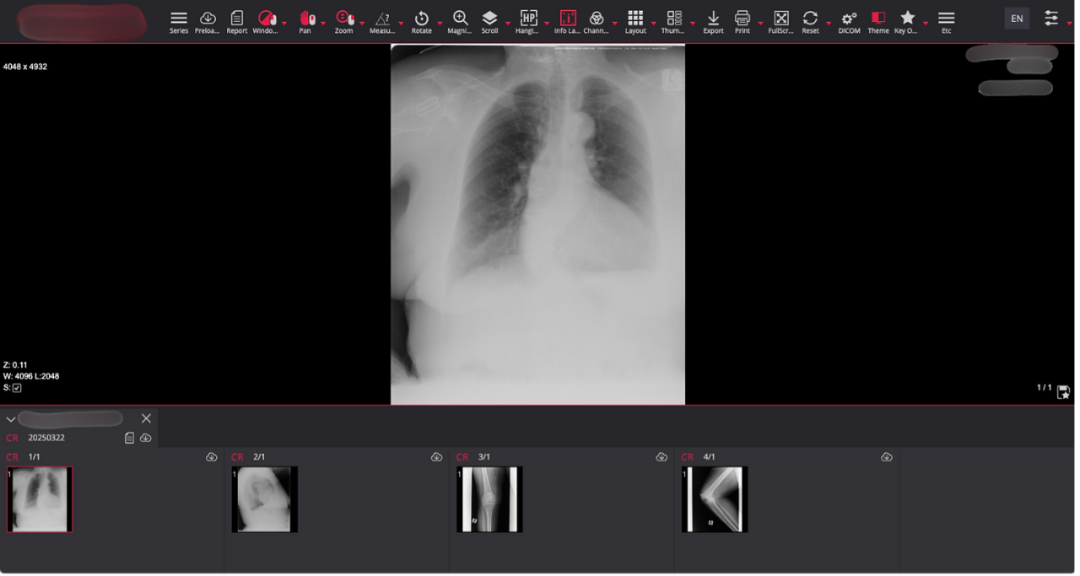

图:包含患者详细信息的胸部、肺部及腿部磁共振扫描图像

泄露的数据样本包括大脑扫描图像和X光片,这些图像通常与受保护健康信息及患者个人身份信息共同存储,可能对患者的保密权和隐私造成双重侵犯。

由于这些扫描仪未进行安全配置,研究人员发现了一些包含患者姓名和扫描日期的大脑图像。采用类似方法,他们还获取了其他多种类型的医疗图像,包括验光师的眼科检查图像、牙科X光、血液检查结果,甚至用于肺癌患者诊疗的详细肺部磁共振图像。被曝光的医疗文件数量之大,令人震惊。